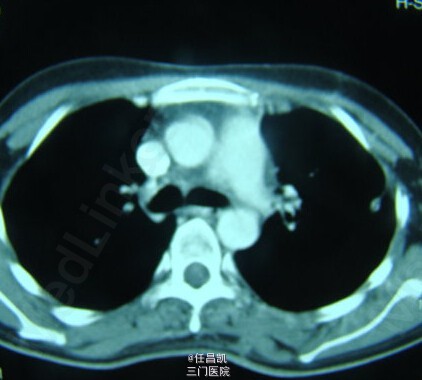

患者女,30岁,因胸闷不适4个月就诊,先后疑诊为肺癌、肺结核等治疗效果欠佳,进入我院。患者发病以来,无发热、咳嗽、血痰、胸痛等。

查体:心肺听诊无异,未见阳性体征。 辅查:CT如图所示。

入院诊断:肺部肿块待查 处理:入院后行手术探查+切除术治疗,术中快速病理检查排除恶性肿瘤,切除病灶,病理和免疫组织化学检查诊断为巨大淋巴结增生症。术后予补液、营养支持等对症处理,患者恢复顺利,复查CT无异,症状缓解遂出院。 出院诊断:胸内Castleman病